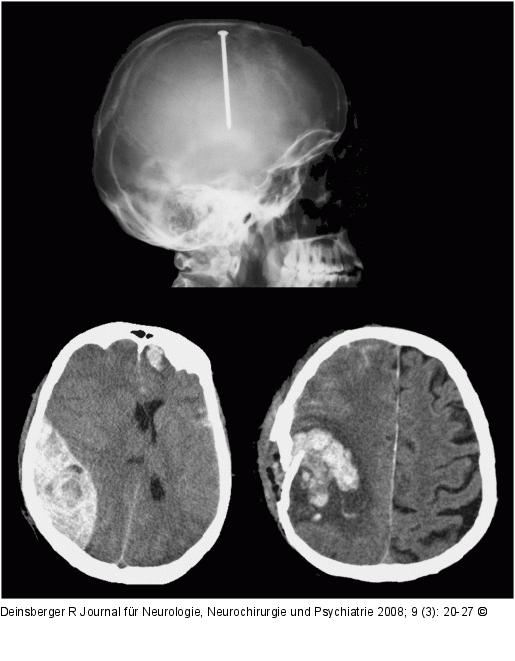

Abbildung 1: Nagelschussverletzung Nagelschussverletzung, Epiduralhämatom und Impressionsfraktur mit Kontusionsblutung |

Abbildung 1: Nagelschussverletzung

Nagelschussverletzung, Epiduralhämatom und Impressionsfraktur mit Kontusionsblutung |